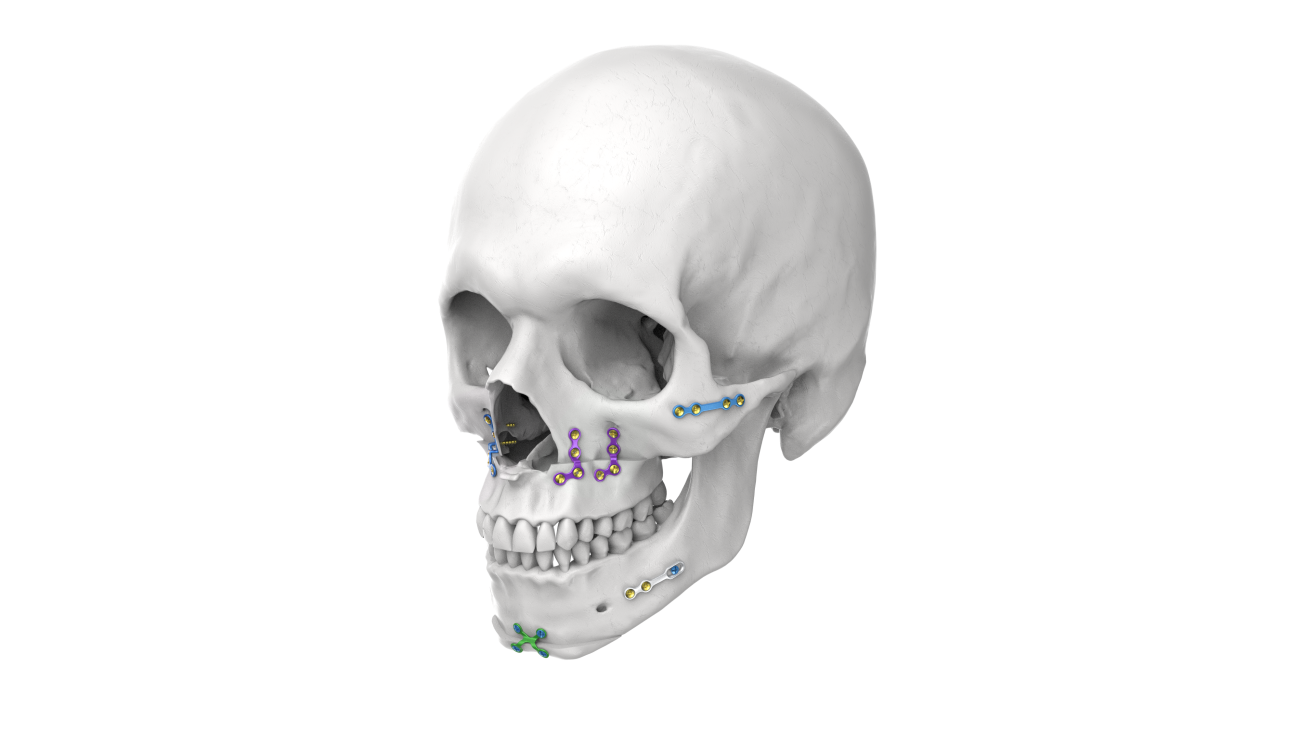

OMF Custom-Made PSI

Our OMF Custom-Made Patient-Specific Implants (PSI) are designed using advanced 3D planning and manufacturing technologies to achieve precise anatomical fit and superior reconstructive outcomes. These implants are ideal for complex facial and mandibular reconstructions.